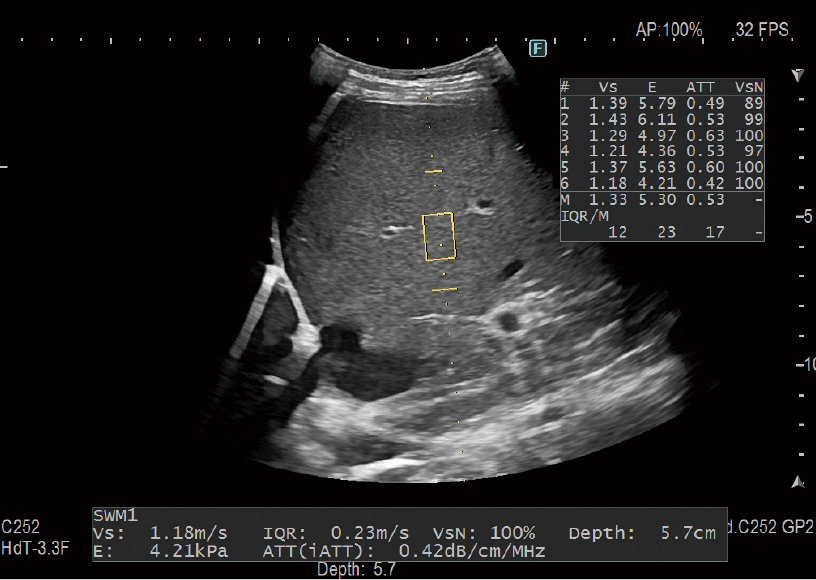

Shear Wave Ölçümü (SWM) / iATT

Doku sertliği, kesme dalgaları oluşturarak ve doku içindeki yayılma hızı (Vs) ölçülerek değerlendirilebilir. iATT, yağlı karaciğer miktarını tahmin etmek için bir indeks (ATT) ölçer. Analiz alanının daraltılması ve ekran kılavuzu sayesinde İB’nin (İlgi Bölgesi) belirlenmesini kolaylaştırır, bu nedenle ATT ölçümüne müdahale edecek çoklu yansımalar ve kan damarları gibi yapılar önlenir.